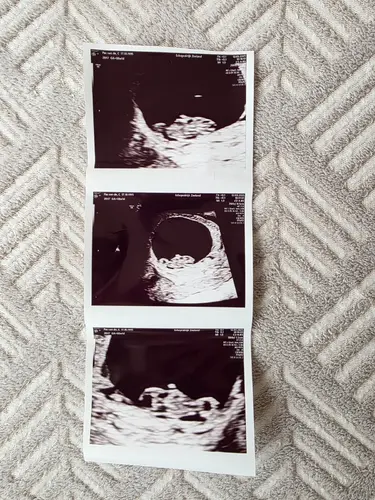

Nog geen kloppend hartje, alleen een vruchtzakje met 5w5d 🥰